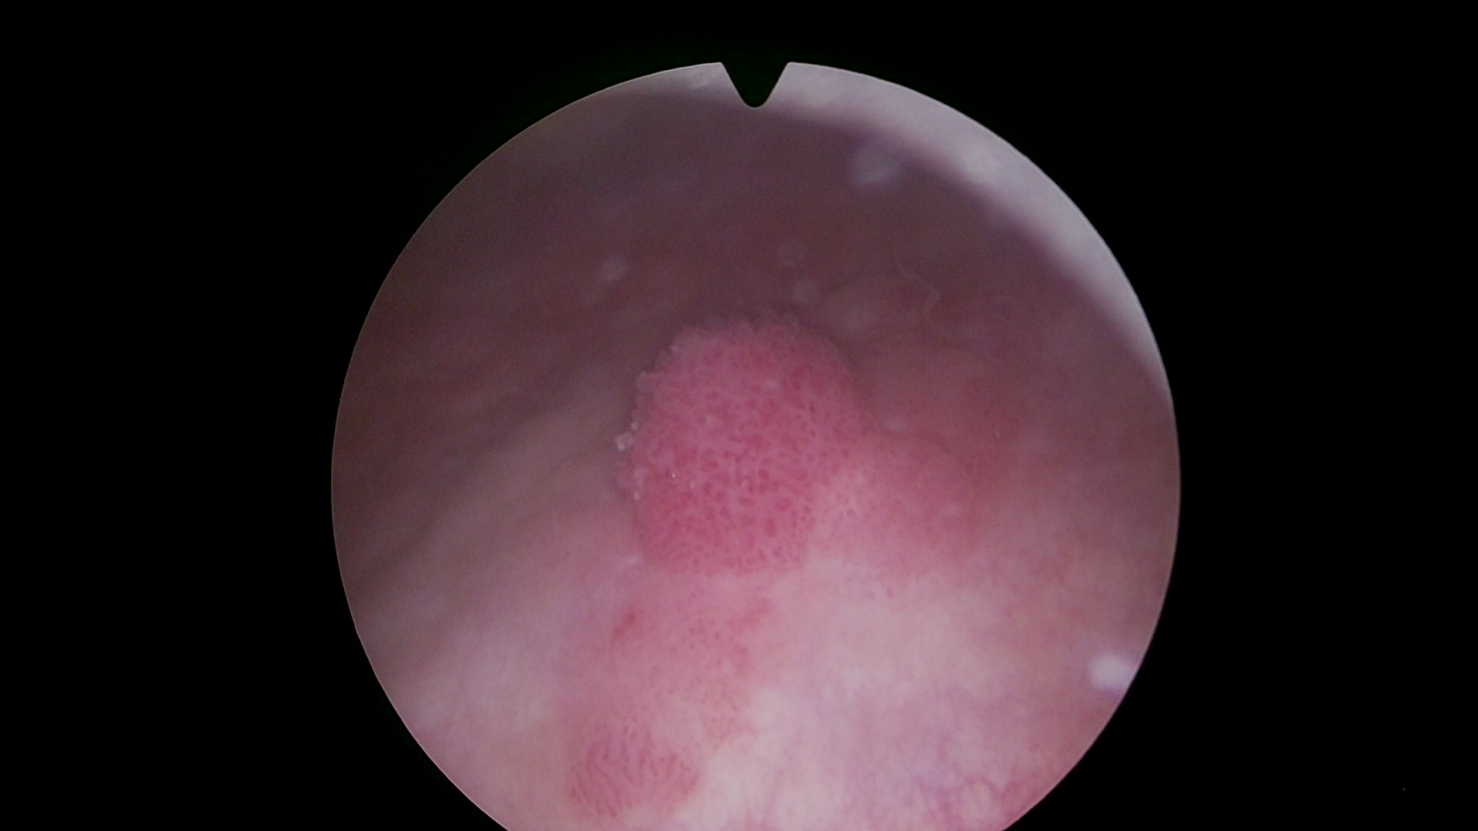

4.膀胱肿瘤切除